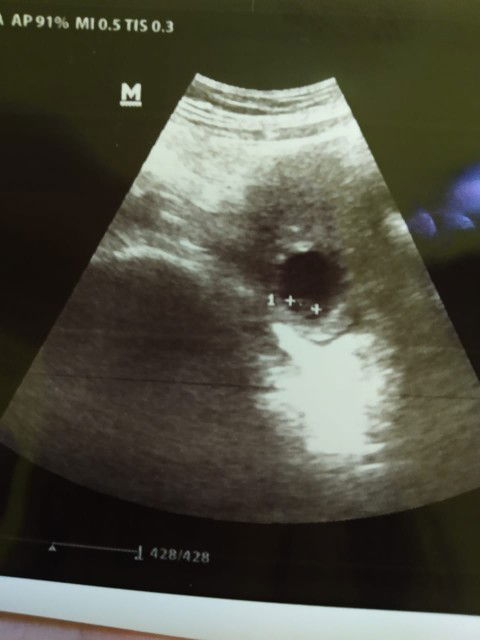

bun saya mau tnya ada gak yg serupa kyak saya. usia kehamilan saya 6w jlan 7w dan tgal 22 usg kantung hamil dan biji janin normal setelah 5hari kantung hamil mengecil dan calon janin tidak kelihatan lagi. itu kenapa ya kira" kalau ada pengalaman serupa gimana ya bun cara perbaiki dan penyebab nya. #bantusharing #jangandibully #Nanya #babyfirst #seriusnanya